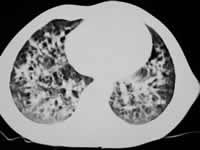

胸片(见图1):两肺广泛分布粗网点状及小斑片状阴影,并可见广泛小囊状透亮影,部分结节内有空腔;上纵隔不宽,纵隔心影无移位,纵隔肺门未见肿大淋巴结及钙化。肺部CT(见图2):两肺广泛间质改变及小泡性气肿,囊大小不一,壁厚薄不同,伴少量实质病变。头颅平片:右眶外上方类圆形局限性骨破坏。肺功能正常。

图2

胸部CT 治疗前

曾津津 副主任医师(放射科):郎格罕细胞组织细胞增生症常有多系统、多器官侵害,包括肺部。对肺部病变X线阳性率各地报告不同,约为50%~70%,这是对肺部弥漫性间质病变的重要鉴别诊断之一。其胸部X线改变随病程及病变浸润程度而异,早期可表现肺纹理增多、毛糙,肺中内带低密度之细网交织影,或呈毛玻璃状;中期典型表现为广泛、密度不一的网结或粟粒状影,可伴小结节或片状浸润,常伴小囊状阴影,易致间质肺气肿和气胸,病变以两肺中上野明显,两侧肋膈角很少受累。当合并肺部感染时更易发生囊性变,炎症吸收后部分囊性变可消失,但网粒状改变更为明显;晚期呈弥漫性肺纤维化,两肺可呈粗大的条索状影,并有明显囊泡形成,最后变成蜂窝肺。该患儿X线改变符合中期典型表现。

本病尚需与其他肺间质病变如急性粟粒型肺结核、特发性肺含铁血黄素沉着症、间质性肺泡炎等鉴别。诊断需结合临床,遇有可疑者尚应作骨骼X线检查,肺间质病变与骨缺损二者对诊断本病有相辅相成、互相印证的作用。该患儿颅骨骨破坏对本病诊断有极大帮助。另外胸部CT尤其高分辨CT扫描能更清晰地显示病灶的分布和细微的改变,亦有助于早期诊断和鉴别诊断。